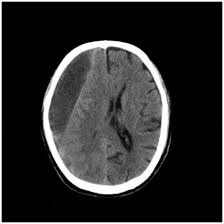

If a chronic subdural is suspected, doctors at NNRC will order a CT scan of the head to check for the bleed and assess its size.